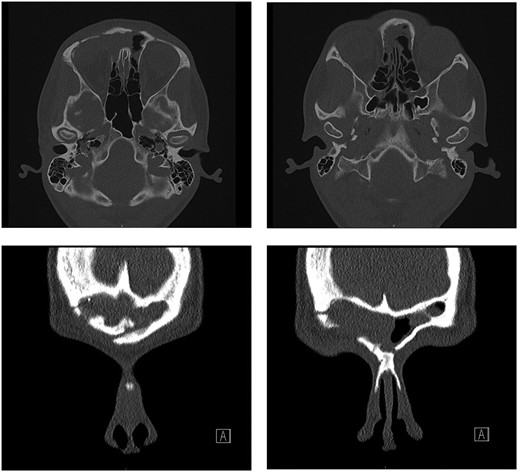

She underwent an external bicoronal approach, frontal sinusotomy with an osteoplastic flap. The frontal sinus was opened and the OF shelled out, including the orbital roof connection. A 3 cm × 2.5 cm defect in the orbital roof, was closed with an irradiated cadaveric rib (Tutoplast ®) graft fashioned to size (Fig. 2). This was overlaid with a pericranial flap. An osteoplastic flap was used to close the frontal sinusotomy, secured with screws.

Combined endoscopic and bicoronal approach with the cadaveric rib graft cut to size to fit and repair the orbital floor defect.